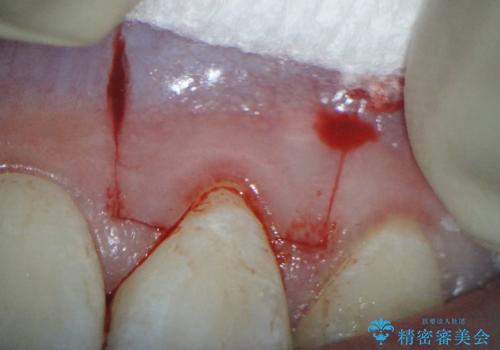

下顎前歯の歯肉退縮 結合組織を用いた根面被覆

口蓋から結合組織を採取して、根面被覆を行いました。